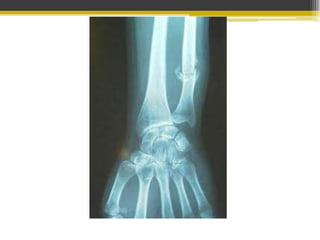

Fractura de la metáfisis distal del radio

A 3 ó 4 cm de superficie articular

Angulación volar de la punta de la fractura

Desplazamiento dorsal del fragmento distal

Puede o no incluir a estiloides cubital

 Caída sobre la mano en hiperextensión

Mantener la longitud radial

 De 6 a 8 semanas

En pacientes con poco desplazamiento o mínima conminución

En Fx conminutas, desplazadas o abiertas no subsidarias de

reducción cerrada ni fijación interna.

Usada en Fx con desplazamiento articular

Yeso postoperatorio según estabilidad